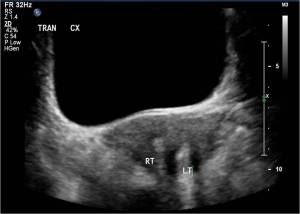

Transverse ultrasound image through the pelvis shows two separate widely splayed uterine horns, which may be seen in both uterine didelphys and bicornuate uterus.

Transverse ultrasound through the pelvis in the same patient at a more inferior section shows two separate cervices, defining this abnormality as a uterine didelphys.

This is the classic appearance of uterine didelphys. Mullerian duct anomalies are classified according to the American Fertility Society system here. Occasionally a uterine horn can become obstructed and cause hematocolpos, or hematometrocolpos.